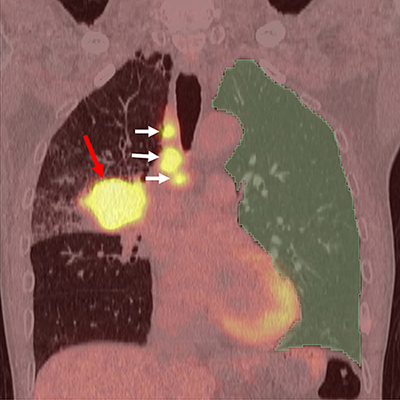

Example of AI analysis of PET/CT images

Using AI, the lung region without cancer on PET/CT images (green-colored region, called noncancerous lung) is automatically extracted. Then, the degree of inflammation within the extracted lung region is calculated. The red arrow denotes lung cancer, and the white arrows indicate lymph node metastasis.